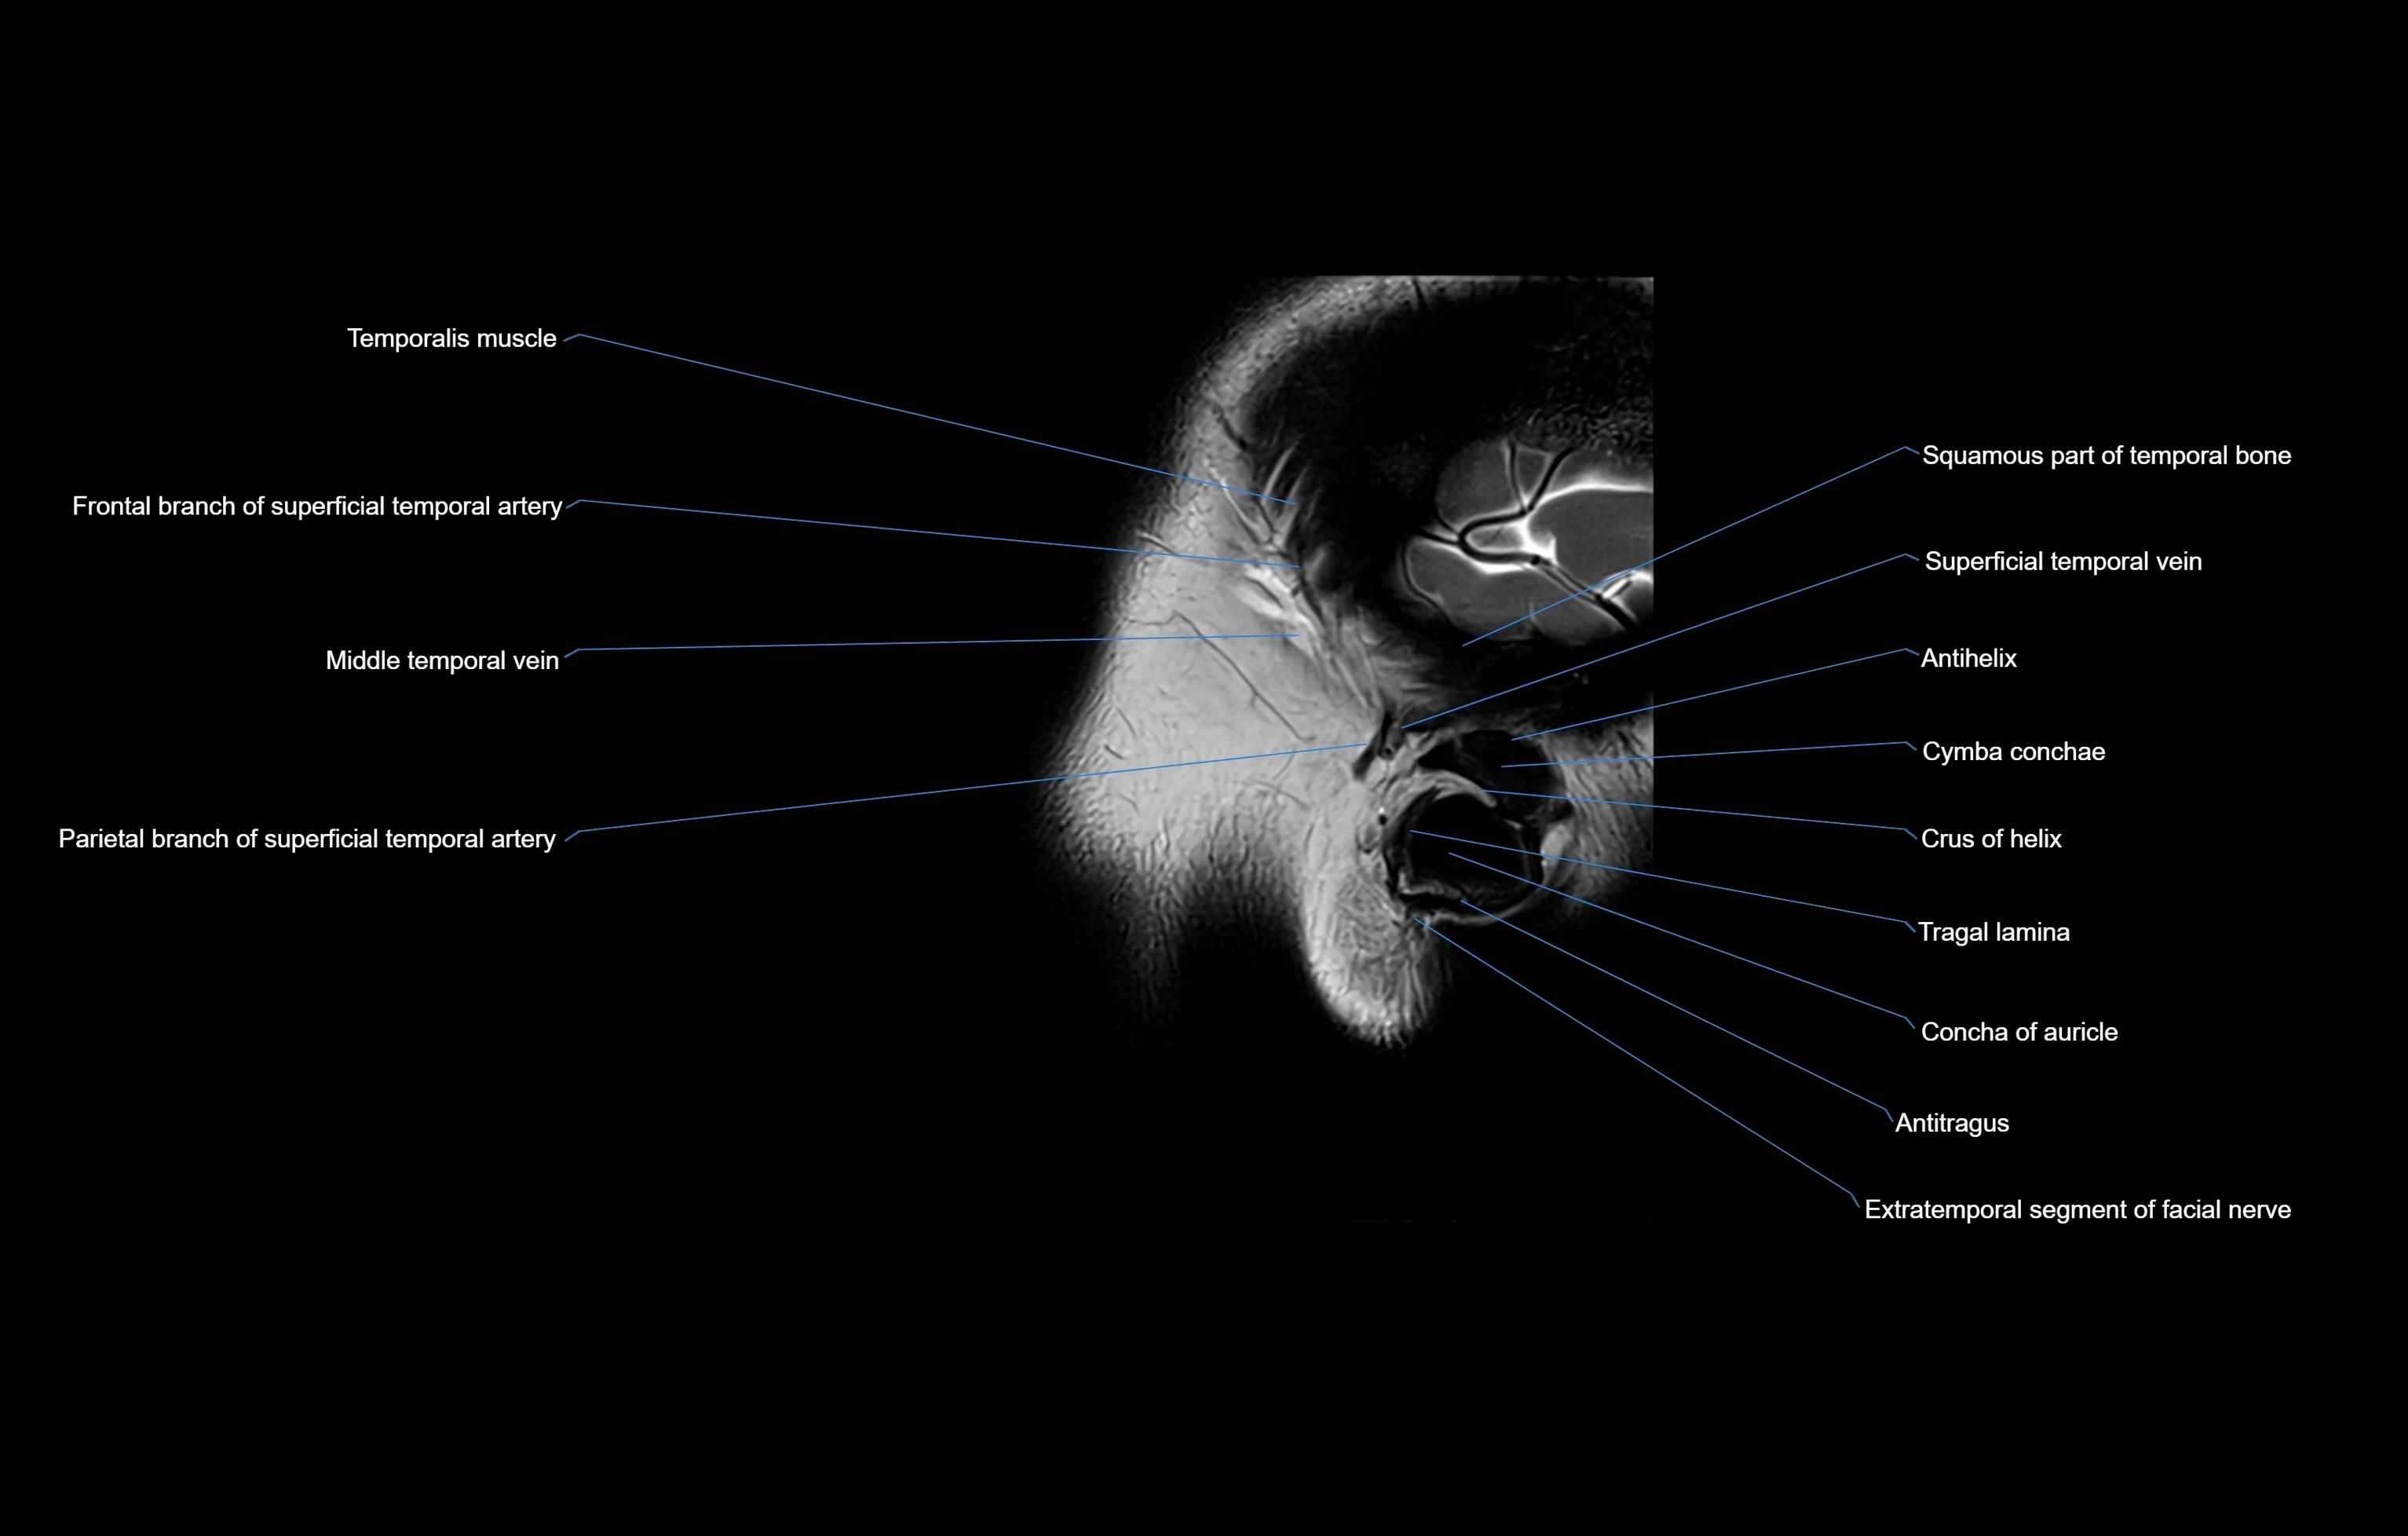

MRI images